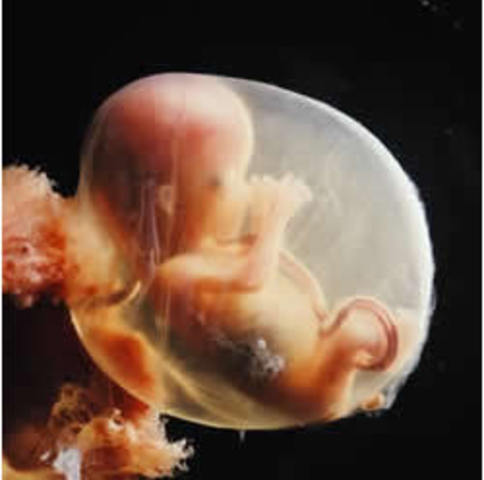

• week 9

week 9

The baby measures about 2.3cm in lenght and weighs less than 2 grams. Eyelids are now completly covering the eyes, but are fused and wont open until week 26. Tiny earholes are now visible. Genitals have formed. Placenta has developed enough to support most of the important job of producing harmones.